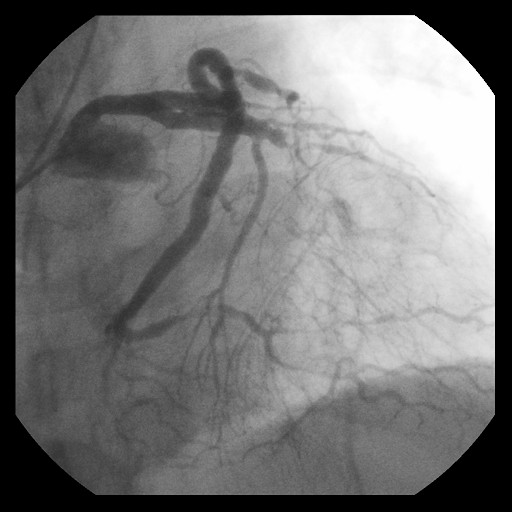

Re-attempted PCI for LAD CTO was planned. The procedure was performed with an 8-Fr, SPB 3.5 SH for the antegrade approach and a 6-Fr IMA for retrograde angiography. Primary antegrade approach was performed because there were no feasible collateral channels. Gaia Next 3 could penetrate the proximal cap of CTO. Since Gaia Next3 could not proceed into the CTO mid portion, the guide wire was escalated to Gaia Next 4. However, Gaia Next 4 advanced into extra plaque space beyond the CTO distal true lumen angiographically. Therefore, we decided to perform tip-detection (TD) method using intravascular ultrasound (IVUS). IVUS revealed that the guide wire proceeded into extra plaque from the CTO proximal portion, although the CTO entry was in the intra plaque space. At first, we tried TD-intra plaque tracking (IPT) in the CTO body. However, Conquest Pro 12 ST (CP-12ST) could not penetrate the CTO body. Therefore, we performed TD-antegrade dissection andreentry (ADR). Eventually, CP12 ST succeeded to puncture the distal true lumen supported by a Caravel. We implanted a drug-eluting stent, which resulted in successful revascularization.